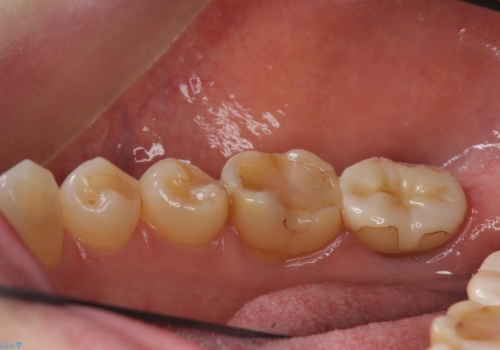

- 奥歯が虫歯になっていたため治療しました。

手前側の歯は前から見えるため、セラミックの詰め物で治療しました。

奥は高さを取るのが難しかったため薄く作れる金属(ゴールド)で治療しています。

- 合計 26.4万円(内訳:右上7 PGAクラウン 11万円(旧料金)、右上6PGAインレー 7.7万円(旧料金)、右上5 emaxインレー 7.7万円)費用は治療当時の料金となります